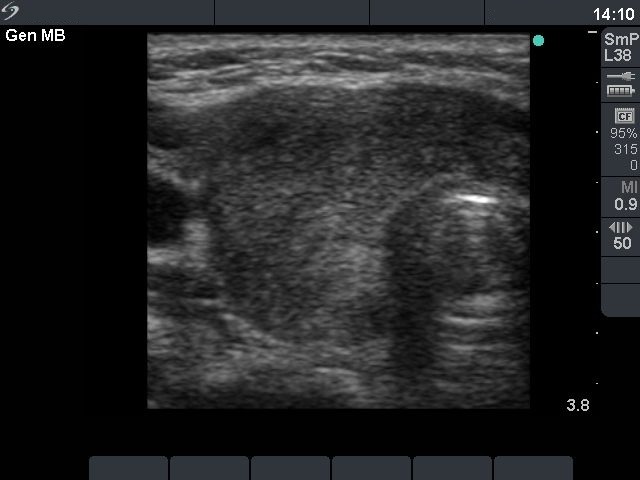

Ultrasonography: diffusely moderately hypoechogenic lobes with several circumscribed, even more hypoechogenic areas with blurred border.